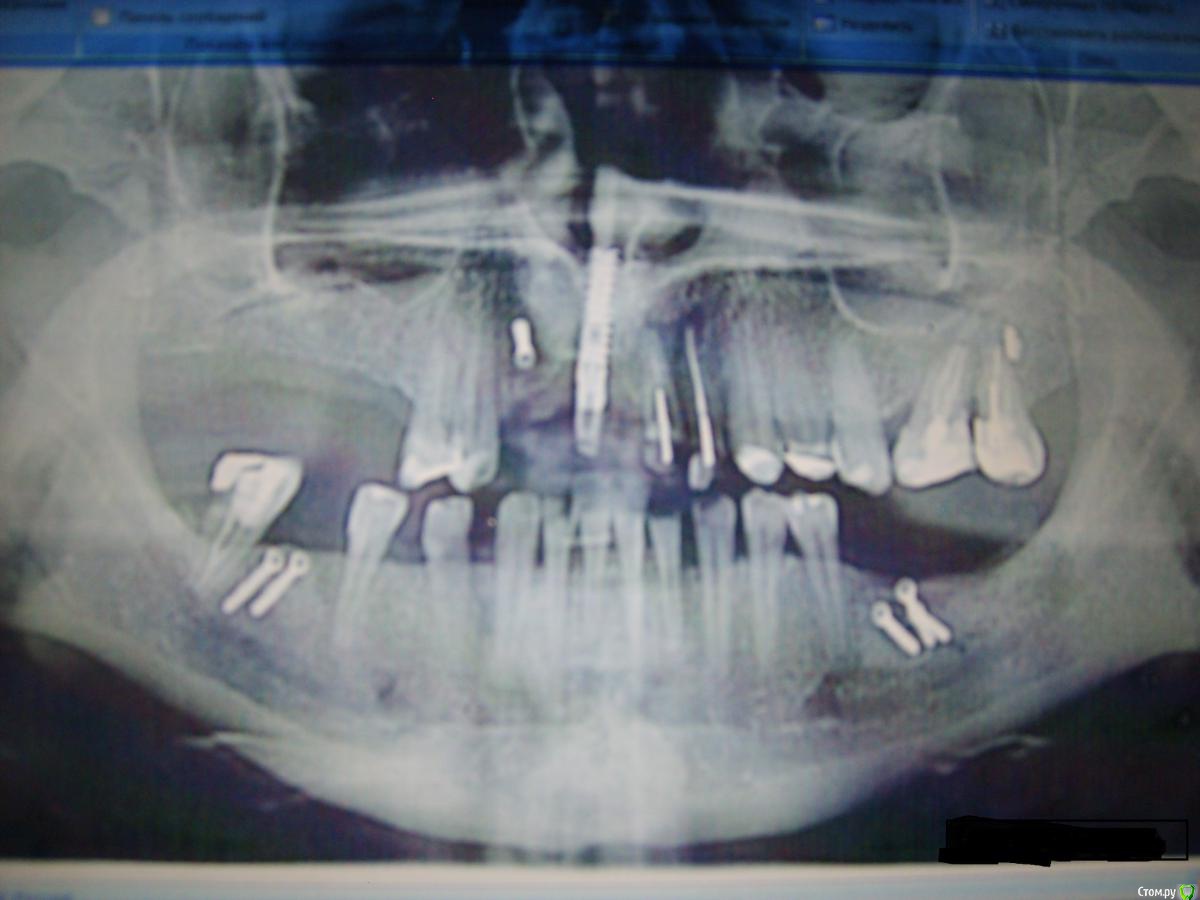

Masha4 Опубликовано 27 декабря, 2015 Поделиться Опубликовано 27 декабря, 2015 (изменено) Уважаемые Эксперты, уважаемые Врачи, здравствуйте! Очень прошу Вашей помощи с планом операций, т. к. запуталась окончательно. В 2015 г. обратилась к хирургу (клиника №1) для комплексного решения своей непростой ситуации.План операции Доктор "озвучил" следующий:1 этап - операция. общий наркоз - РВК 21, 22; -лоскутная операция 25, 26, 27 -удаление импланта 11 -костная пластика 3 участка (забор из повздошной кости)2 этап - имплантация 8-9 едениц:3 этап - постоянное протезирование (через 4 мес.). По факту операции (май 2015г.) я получила:-удаление 12-костная пластика 4 участка ( зоны 12, 15-16-17, между "разъехавшимися" 45 - 46, 36-37-38). Слизистую щеки пришивали на десну.Имплант 11 оставили. Сказали он "стабилен", при постоянном протезировании установить коронку с искусственной десной. Июль 2015. Из импланта начал немного подтекать гной. Зона 11-12, периодически небольшое жжение,воспаление, дискомфорт. Доктор сказал что причина - 21.Про имплант 11 сказал что они его в мае попытались выкрутить, но не смогли. Когда он будет ставить импланты, удалит 11 и сразу же на его место установит другой. Костная пластика в этой зоне не нужна! (место позволяет установить другой) В двух других клиниках (клиника №2, №3) сказали - причина все-таки имплант 11, т.к. вокруг него полость. В настоящее время, Хирург, делавший ОП, настаивает на операции. Срочно. Иначе уйдет кость.За одну операцию(предмедикация-удаление 21, 22--имплантация 8-9 единиц (21,22,12, 11(по ситуации), 15, 16, 17, 36, 37, 38, между 45 и 46)-если получится! - удаление импланта.( План в бумажном варианте не составляется. По фронту Доктор сказал: пока не вскроешь - не поймешь. Но импланты на жевательную группу установят 100% ) Клиники №2 и №3 рекомендуют следующий вариант:1. установить импланты на жевательную группу2. через 1-2 мес. заняться фронтом (за одну операцию)-удаление старого импланта 11-установка имлпанта 12-попытаться сделать РВК 21, 22.-если РВК не получится удаление-имплантация.3. в зоне 11 возможно, больше ничего не делать (живого места нет) При постоянном протезировании мост 21-12 на имплантах. Уважаемые Врачи,очень прошу Вашего заключения и оценки моей ситуации.Что бы Вы мне посоветовали, на что еще нужно обратить внимание?Очень Вам благодарна! Большое спасибо! Изменено 27 декабря, 2015 пользователем Masha4 Ссылка на комментарий

IvanK Опубликовано 28 декабря, 2015 Поделиться Опубликовано 28 декабря, 2015 по РВК: начните с терапевта План лечения кто составлял? Ортопед принимал участие? В переднем отделе, если хотите эстетику, имплантат нужно удалять Ссылка на комментарий

Masha4 Опубликовано 28 декабря, 2015 Автор Поделиться Опубликовано 28 декабря, 2015 IvanK, Большое спасибо что отвечаете. Ортопед в составлении Плана не участвовал. В клинике, где проводили ОП "костная пластика" не запросили план Ортопеда ( КТ не смотрели, хотя у меня есть До и После).Справедливо будет сказать: этот Хирург - единственный в городе, кто занимается костной пластикой в больших объемах. После множества консультаций, меня к нему направили из другой клиники. Был большой костный дефект. говорили что решить его можно только в условиях стационара. Если честно, мне уже не надо эстетики, но в районе импланта есть воспаление.Почему-то Доктор на первой операции не смог его выкрутить. И сейчас как-то неуверенно говорит про его удаление. Уже не знаю что думать, Доктор не склонен объяснять.Может имплант в принципе невозможно удалить? Или у меня будут большие проблемы после его удаления? И поэтому пока так неопределенно? По РВК - спасибо за совет, попробую найти терапевта. Врач Ортопед у которого планирую делать тотальное протезирование по окончанию лечения (очень ему доверяю) работает в другой клинике. (Но там свой Хирург). Я правильно понимаю?: - мне необходимо обратиться к Ортопеду, составить с ним план лечения и дальше сотрудничать уже с его Хирургом по имплантацииСпасибо огромное. Ссылка на комментарий